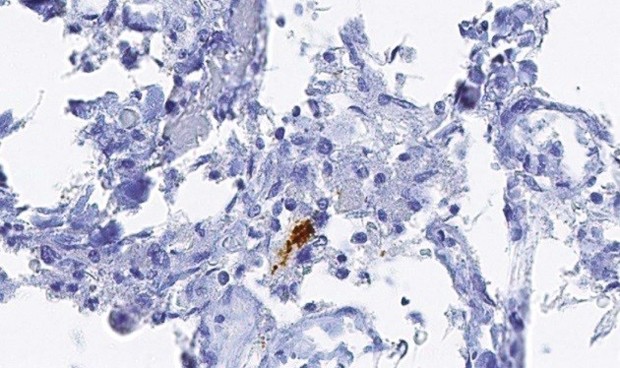

Los investigadores han hallado que estos virus manipulan, exactamente, una antigua especie de ARN, originada hace varios millones de años, llamada ARN del satélite humano II (ARN HsatiiI). El ARN Hsatii normalmente está inactivo, pero los virus por herpes y las células cancerosas, fundamentalmente, han aprendido a activarlo y utilizan este ARN para manipular su entorno con el fin de ir creciendo hasta invadir el cuerpo.